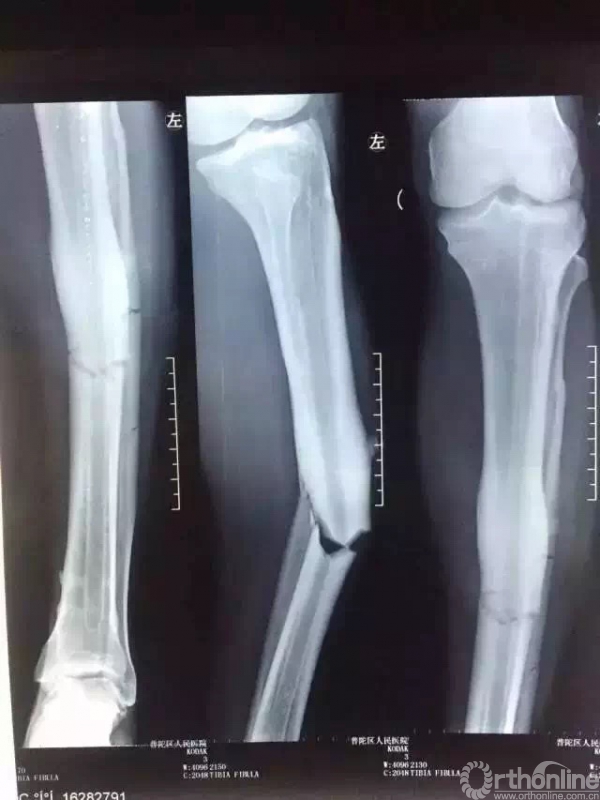

2016年7月17日,球员登巴巴在中超比赛拼抢中遭遇重伤,被诊断为左胫腓骨中段骨折。

急诊X光片

登巴·巴(Demba Ba)1985年5月25日出生,是一名在法国出生的塞内加尔足球运动员,司职前锋,曾效力英超的纽卡斯尔联、切尔西和贝西克塔斯,现效力于上海绿地申花足球俱乐部。2015年中国足协杯最佳球员。2016年7月17日,中超第17轮比赛第63分钟,登巴·巴在对抗中倒地,导致左胫腓骨中段骨折。